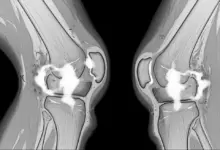

O edema ao redor de um ligamento representa acúmulo de líquido e alteração inflamatória nos tecidos vizinhos, que pode aparecer após torções, impactos, movimentos bruscos ou sobrecarga repetitiva.

Em alguns casos, o ligamento permanece íntegro e o edema reflete apenas uma agressão local. Em outros, o exame pode estar mostrando a repercussão de uma lesão parcial ou completa.

Depois disso, a ressonância ajuda a detalhar as estruturas envolvidas. Radiografias também podem ser indicadas, principalmente quando há trauma importante, dor persistente ou suspeita de lesão óssea associada.